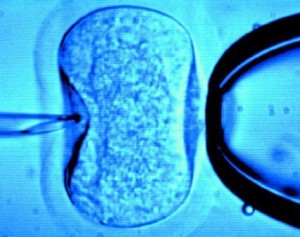

Quando l’infertilità della coppia è dovuta alla qualità dello sperma, può succedere che anche in un ambiente così “semplice” come quello ricreato in laboratorio, dove non ci sono gli ostacoli che possono essere trovati nel corpo della donna, la fecondazione risulti troppo difficile. Si può procedere allora all’inserimento dello sperma direttamente nell’ovulo (iniezione intracitoplasmatica dello spermatozoo).